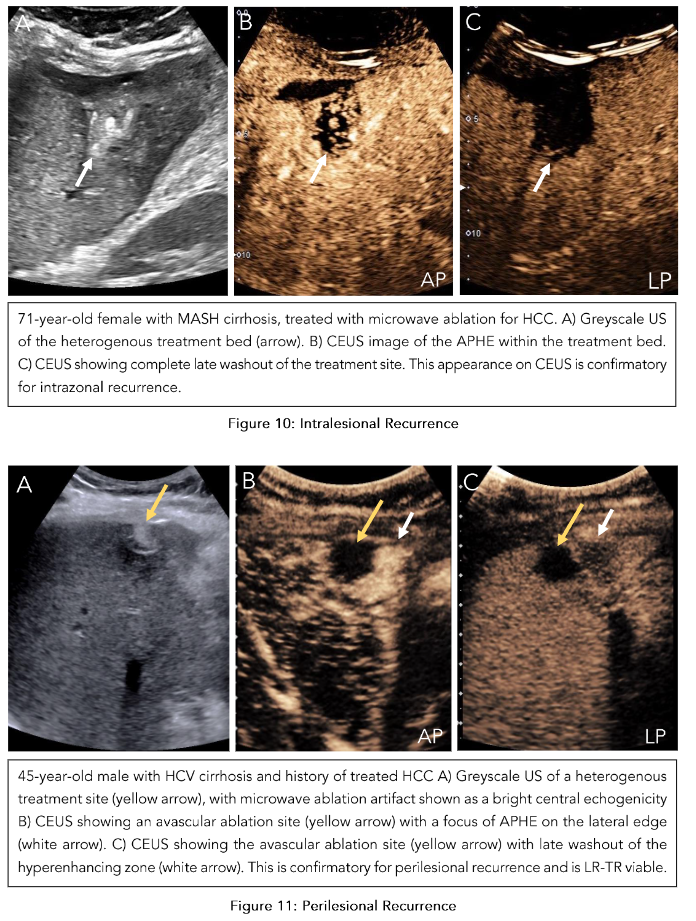

Intralesional viability:

If there is no enhancement within the ablation bed, it indicates the absence of a viable tumor. Uncertain viability is characterized by arterial phase hypoenhancement (with or without washout), while hyperenhancement or isoenhancement (with or without washout) suggests the presence of a viable tumor (Figure 10). -

Perilesional viability:

Absent viability is characterized by homogeneous enhancement of the ablation margins compared to the rest of the liver. Uncertain viability is characterized by arterial phase hyperenhancement without washout, isoenhancement with washout, or hypoenhancement. The presence of a viable tumor is confirmed by hyperenhancement with washout (Figure 11). Once both these categories are assessed, an overall treatment response score is determined based on their respective contributions: